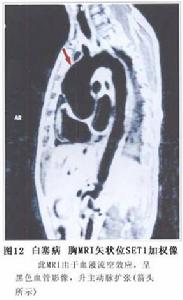

血管造影可發現腎動脈、腸系膜動脈、腦動脈等不同部位的血管呈節段性狹窄性改變(圖12,13,14,15)。